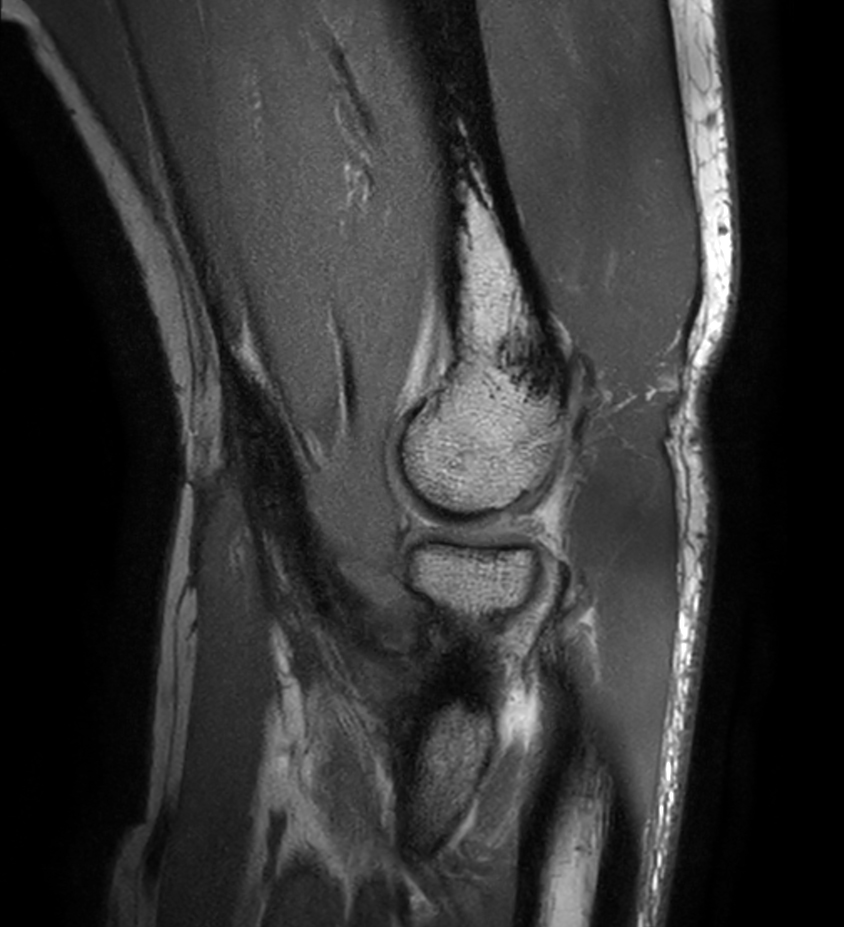

Coronal T1w mDIXON XD TSE (Partial FatSat)